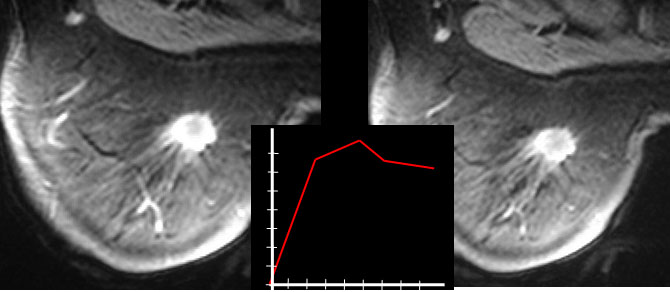

SIGNO DEL LAVADO PERIFÉRICO EN LA MAMA

Signo de cáncer de mama en el estudio de Resonancia Magnética con gadolinio. La periferia del nódulo muestra un aclaramiento del contraste más rápido que el centro (similar al signo del lavado periférico en el nódulo hepático).

Este signo en el cáncer de mama tiene una baja sensibilidad (51 %) pero una especificidad del 100%.

Las imágenes corresponden a una resonancia de mama con gadolinio, en las que vemos un nódulo de márgenes irregulares con realce periférico y una zona central hipoatenuada. Un corte posterior en el tiempo pero en el mismo plano -a la derecha- muestra el adelgazamiento del anillo periférico de captación. La gráfica ilustra la rápida captación del contraste (pendiente ascendiente) y el lavado posterior (pendiente descendente).